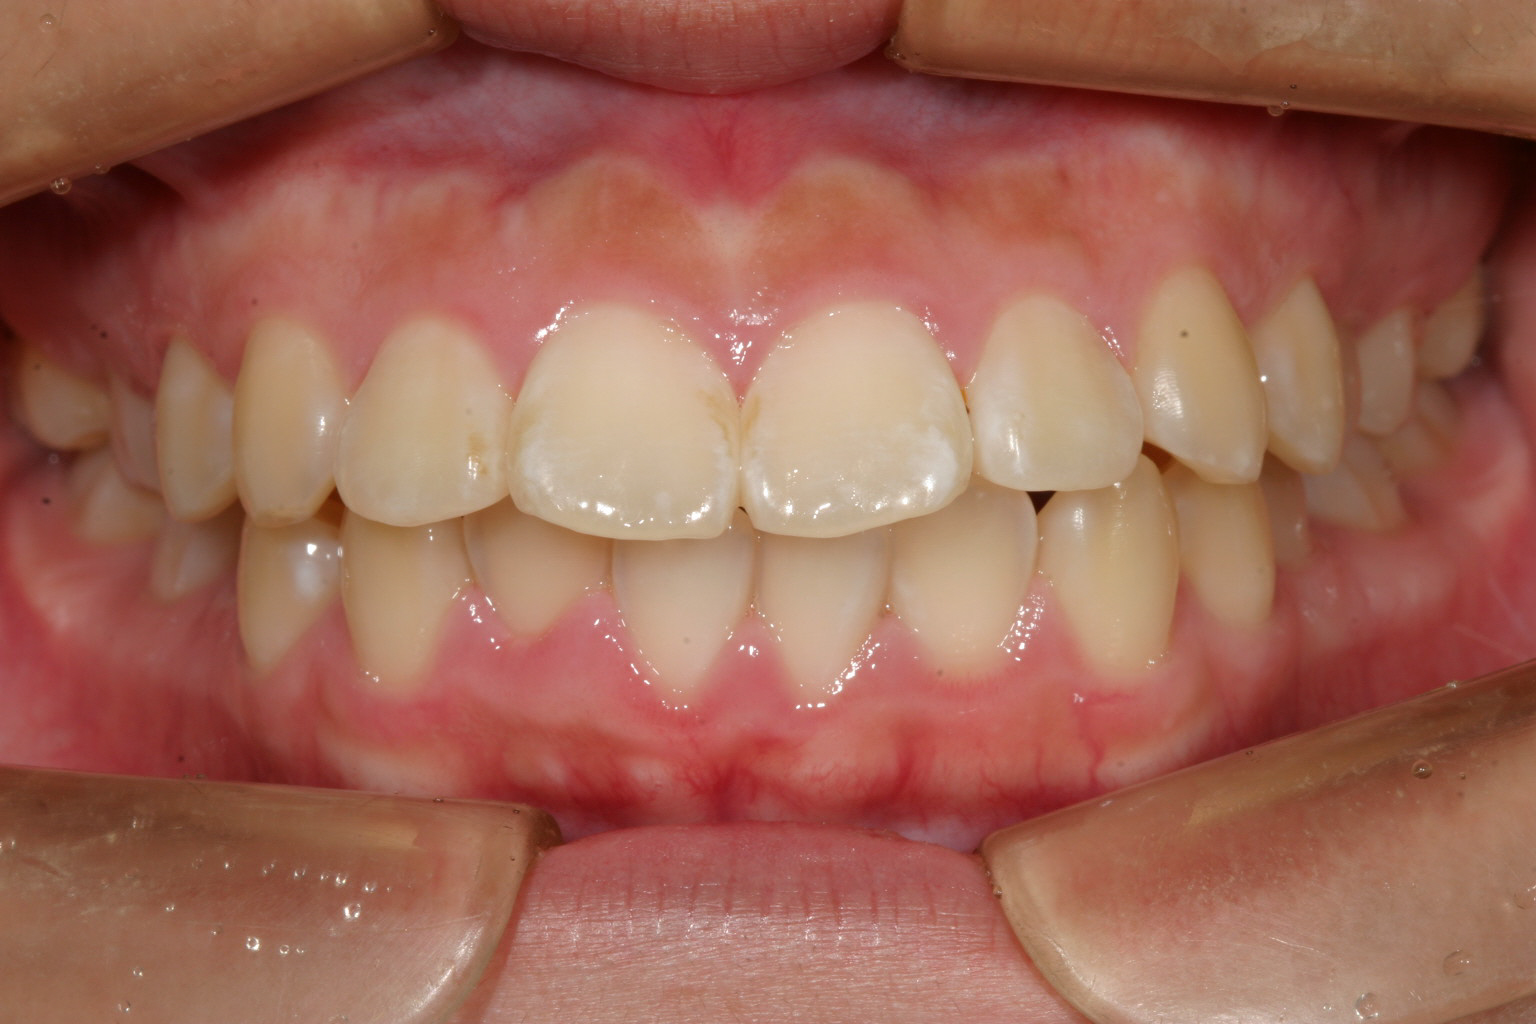

前歯部に少し乱れが有ります。

かなり前歯がでっぱってます。